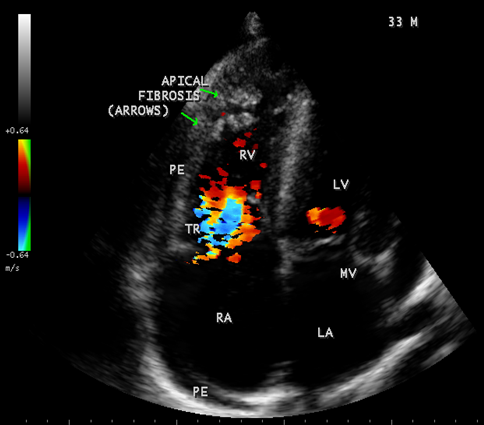

Figure 30: showing thick fibrous strands in the right ventricle with mild pericardial effusion suggesting right ventricular endomyocardial fibrosis in a 33-year old male.

Figure 31: showing tricuspid regurgitation with thick fibrous strands in the Right ventricle in a 33-year old male in RV EMF.